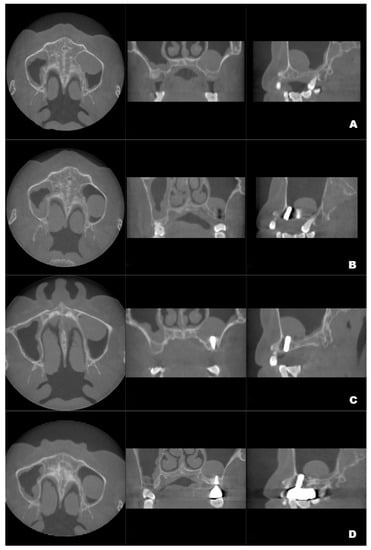

Figure 2.

The volume changes and maximum diameter changes in the axial, coronal and sagittal planes of the patient’s left maxillary antral pseudocyst in the preoperative CBCT image (A) and the follow-up CBCT examinations in 6 (B), 12 (C) and 22 months (D), respectively.

Although the final crown restoration (second procedure) was planned for 6 months after the first procedure, it was delayed until 10 months because of an outbreak of COVID-19. A CBCT scan at the 6-month follow-up showed that the implants had been correctly placed in the augmented sinus, resulting in osseointegration without mobility (Figure 3B). CBCT scans at 12 months and 22 months showed stable bone levels around the implants (Figure 3C,D). The patient reported no discomfort or other complaints in relation to the implants or the maxillary sinus, and no fluid leakage was evident on the incision line during follow-up. However, a comparison of the preoperative CBCT scans with the postoperative scans conducted at 6, 12, and 22 months revealed pseudocyst drift in the left maxillary sinus (Figure 4). At 6 months after surgery, the pseudocyst had moved posterolaterally from the preoperative position near the anterior medial maxillary sinus, then returned to its original position at 12 months. However, it had remigrated to the posterolateral position at 22 months.

Figure 3.

Preoperative CBCT (A) and follow-up CBCT images (6 months (B), 12 months (C), and 22 months (D)) of the patient’s left maxillary antral pseudocyst in the axial, coronal, and sagittal planes.

The pseudocyst volume was manually segmented using 3D Slicer and corrected by a professional radiologist [19]. Measurements of the maxillary sinus pseudocyst revealed that its volume decreased from 3.795 mm3 before surgery to 2.370 mm3 at 6 months post-surgery; it gradually returned to the preoperative volume at 12 months (3.439 mm3), then decreased to 2.930 mm3 at 22 months (Figure 2).